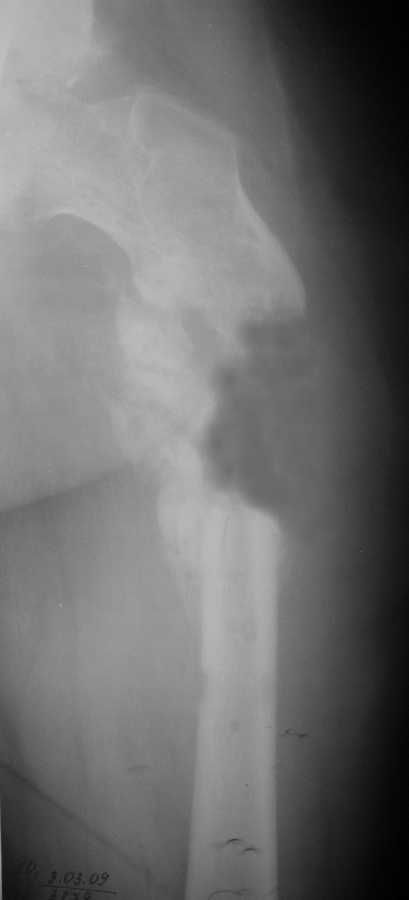

Уважаемые коллеги, у пациента 26 лет имеется дефект в\з бедренной кости образовавшийся в результате СНЭ по поводу травматического остеомиелита

Также имеется травматическая деформация таза с трансвертлужным переломом на стороне дефекта. Планируется замещение дефекта транспортом кости.Хотелось бы услышать ваши советы по поводу оптимальной компоновки АВФ (стержневой, спице-стержневой), есть ли необходимость в дополнительной фиксации за кости таза?

Дефект бедра транспортом тут можно пока не замещать, это долго, муторно, и, главное, не решит проблему создания опорной и безболезненной конечности. Остеосинтез бедра тут одна из подзадач. И решить ее можно относительно быстро - восстановить ось бедра аппаратом (можно как спицевым, так и стержневым) за 10-15 дней, и

сделать закрытый интрамедуллярный остеосинтез. В дефекте есть признаки костеобразования, так что вполне ожидаемо сращение.

Вопрос о АВФ обксловлен конституциональными особенностями больного и относительно коротки проксимальным фрагментом.

4. Дефект бедра сегментарный - в ходе операции удалён фрагмент бедренной кости до 7 см.